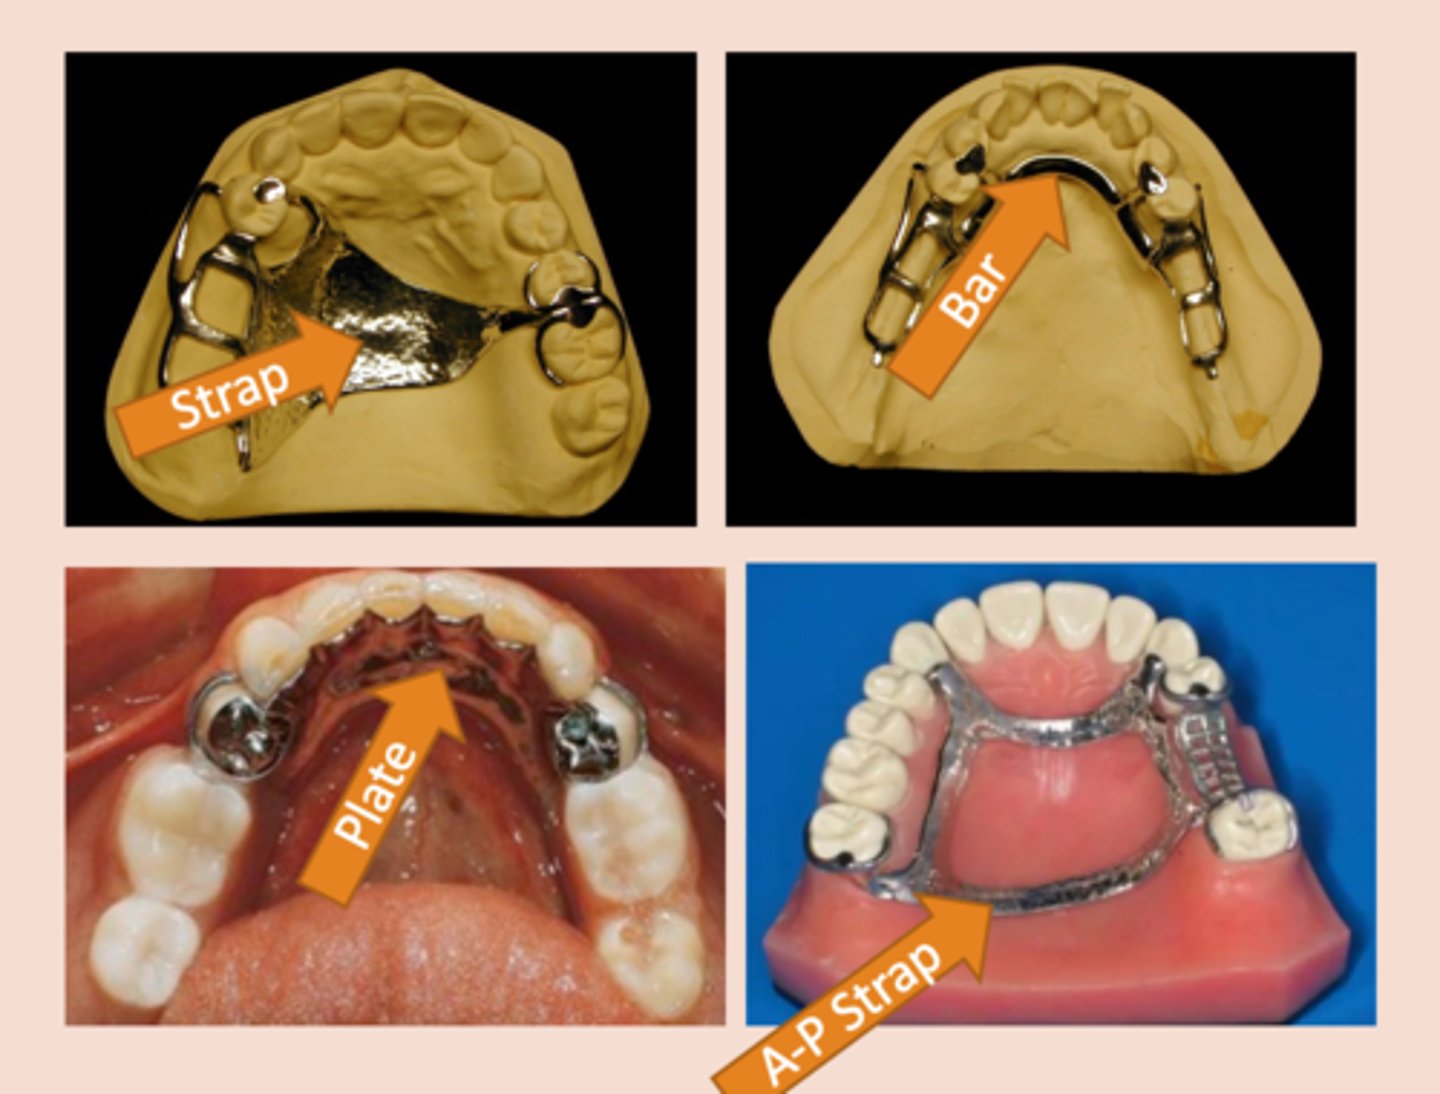

Major connector

The part of the removable partial denture that joins the components on one side of the arch to those on the opposite side, Aid in cross arch stabilization, transmitting functional loads from one side of the arch to the other

Full palatal plate (major connector)

indicated for maximum tissue support. Use in long distal extension cases or if anterior teeth are anticipated to be lost.

Indicated if the primary abutments are periodontally involved, or in cases with a shallow palatal vault or flabby tissues.

Open plate major connector